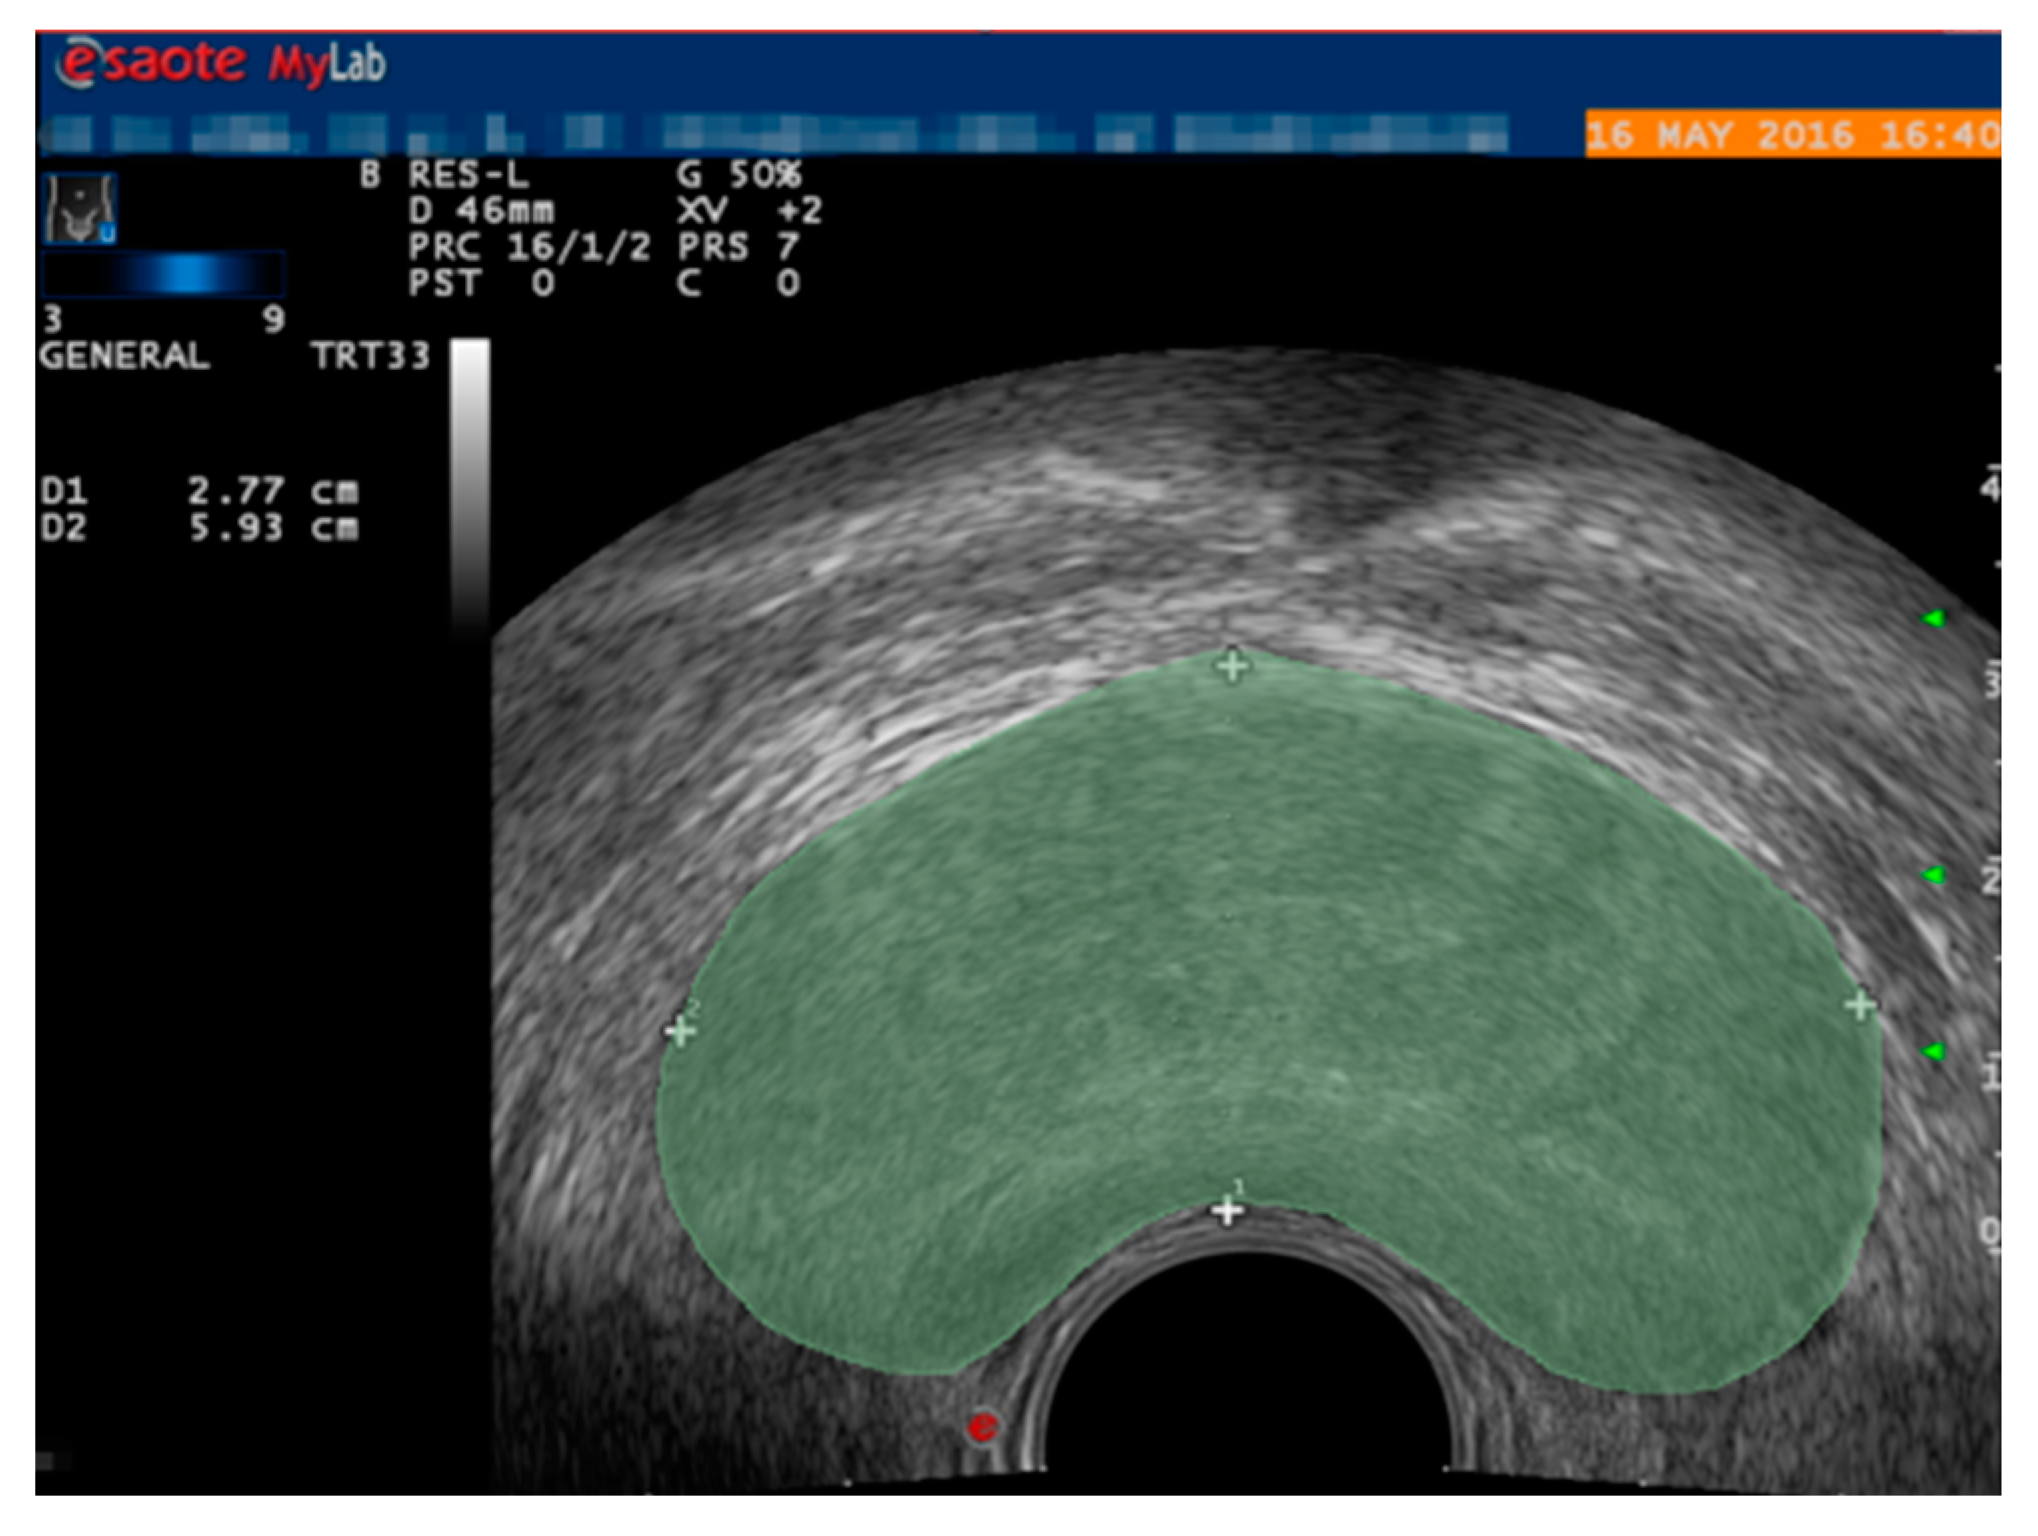

2.1. Data Preprocessing

3.1. Dataset